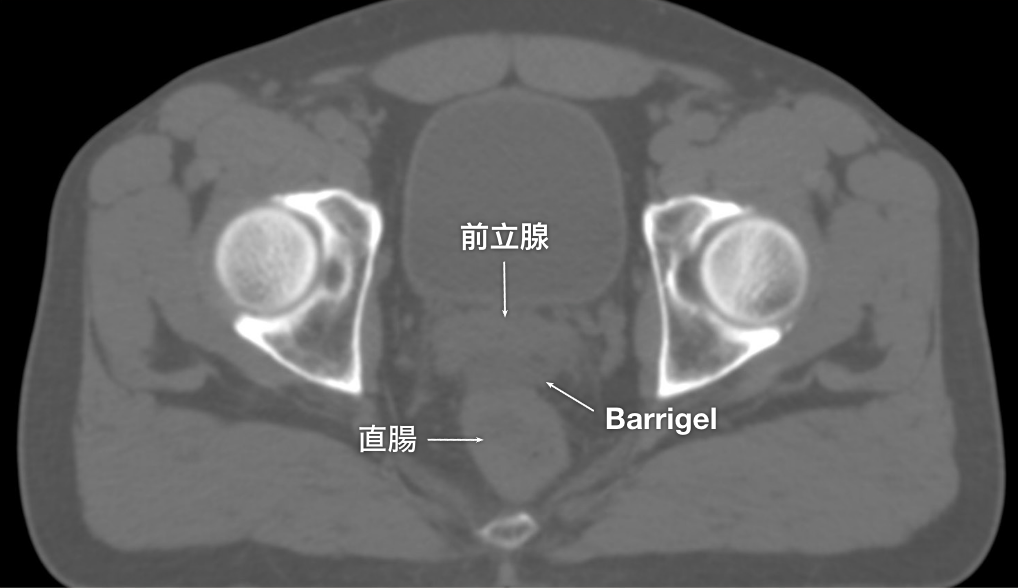

CT画像

CT画像提供:Suraj Singh, MD

Radiation Oncologist, Colorado, United States